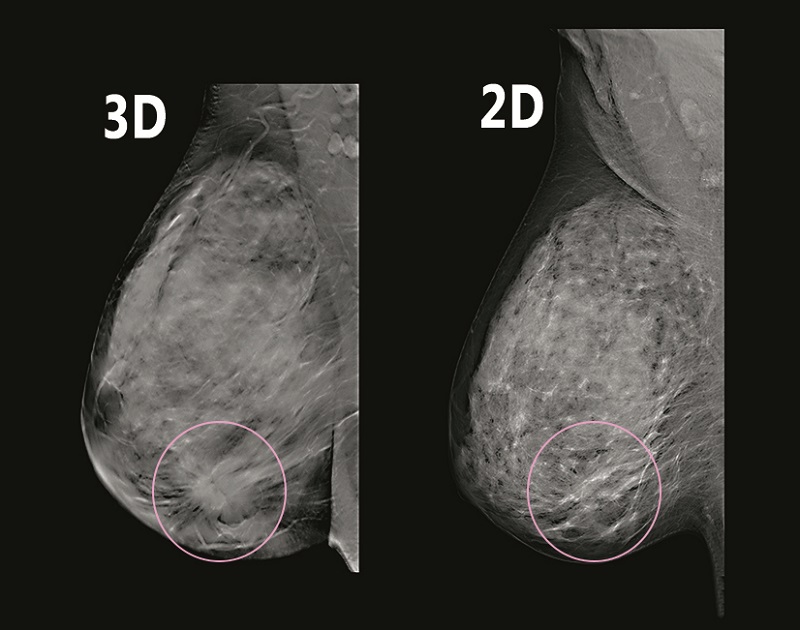

Holigic 3D mammography

Holigic 3D mammography دستگاه ماموگرافي ديجيتال دوبعدي و سه بعدي (توموسنتز) اولين دستگاه مورد تاييد در بررسي هاي كلينيكي ميباشد.